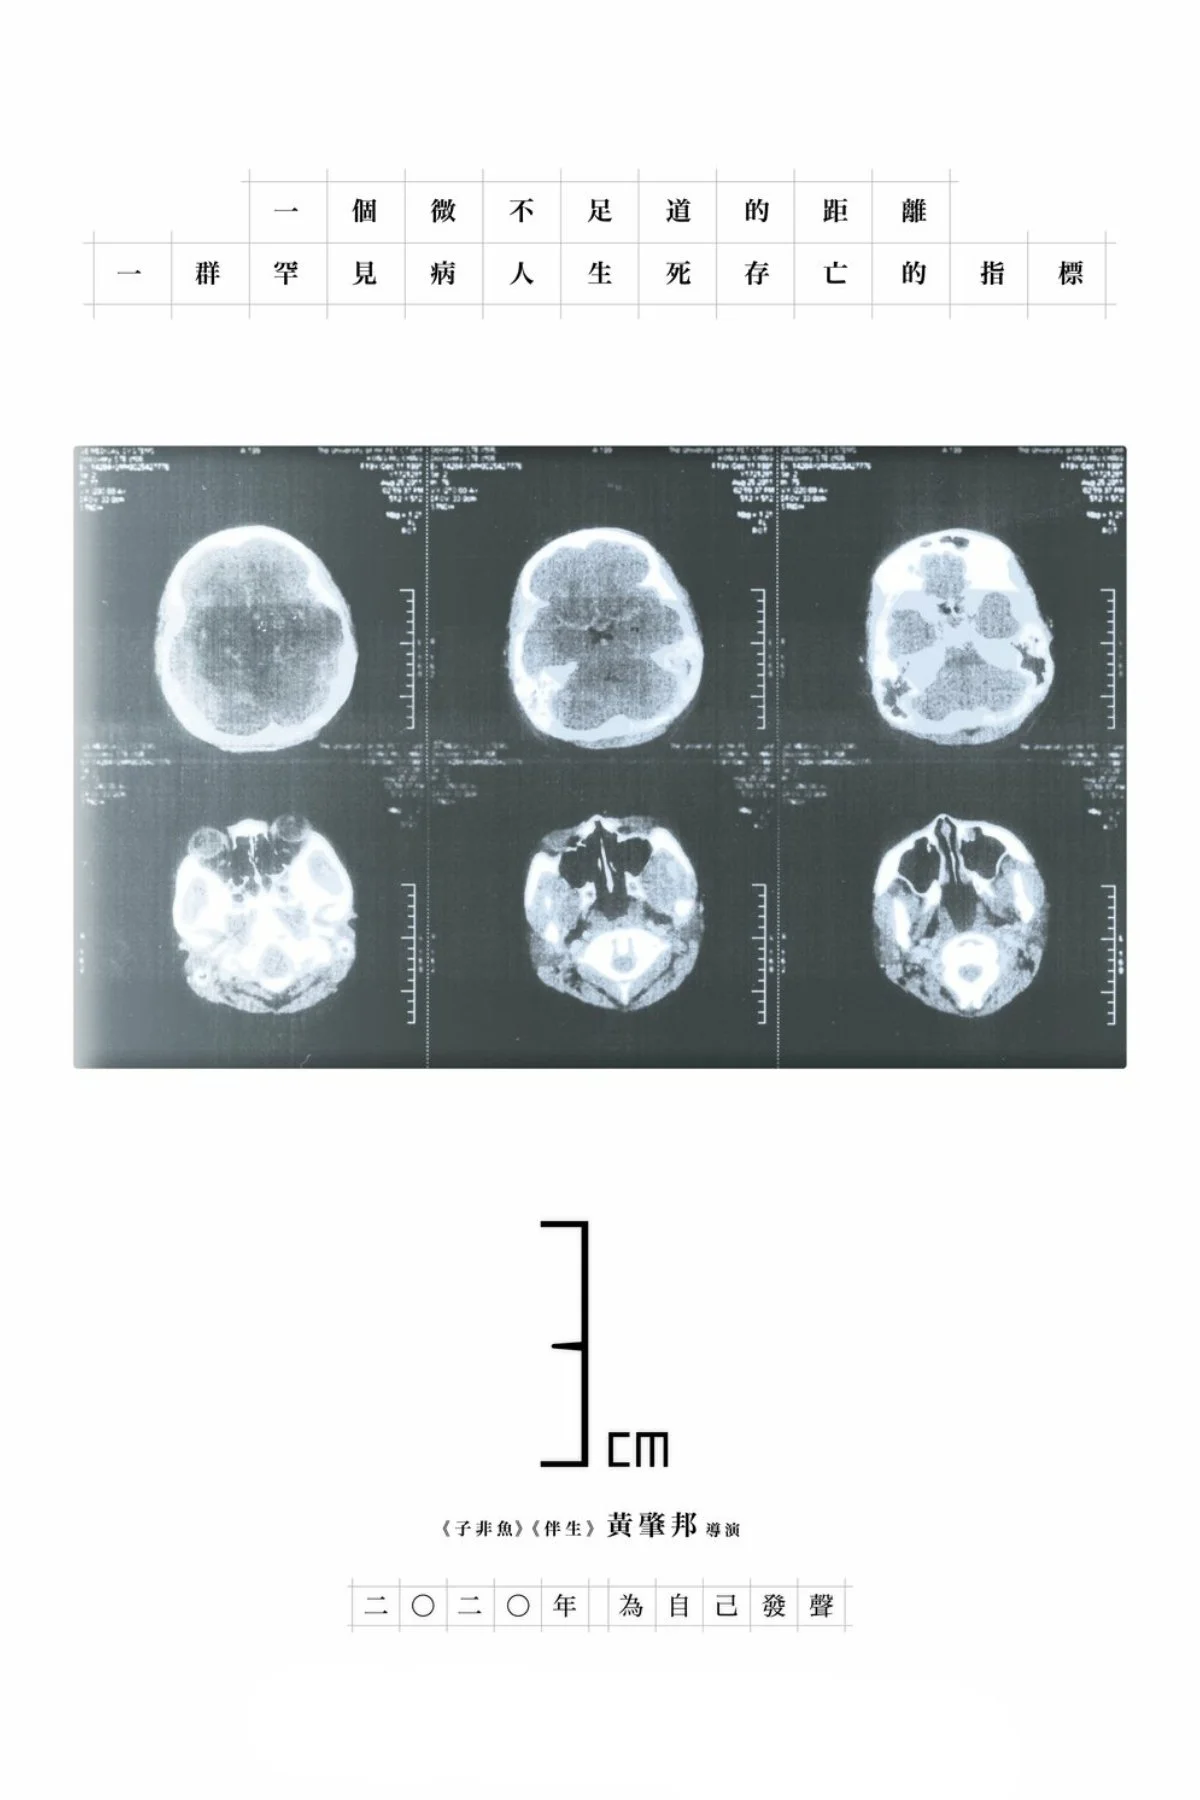

توبروز اسکلروزیس کمپلکس (TSC) یک اختلال ژنتیکی است که باعث رشد تومورهای غیرسرطانی در بخش‌های مختلف بدن می‌شود. با این حال، دولت هنگ‌کنگ در اجازه دادن برای درمان این بیماری به‌ویژه در زمینه تسهیل مقررات داروهای درمان‌کننده تومورها کند عمل کرده است. کارگردان وونگ سیو-پونگ در این مستند دل‌خراش، دوربین خود را به سوی سیستم پزشکی هنگ‌کنگ نشانه رفته و داستان یک بیمار جوان TSC را روایت می‌کند که مادرش را نیز به دلیل همین بیماری از دست داده است.